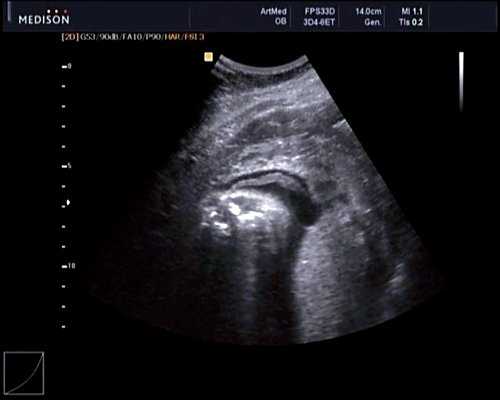

Беременная М., 21 года. Впервые обратилась в клинику в срок 20 нед беременности. Исследование проводилось на аппарате SonoAce-R7 (Samsung Medison) с использованием режима поверхностной объемной реконструкции 3D/4D. При изучении позвоночника плода в трех плоскостях костных деформаций не выявлено. В грудном отделе позвоночника обнаружено тонкостенное кистозное образование с анэхогенным содержимым, стебельчатой формы (рис. 10-12). Степень "прозрачности" содержимого была выше околоплодных вод, что позволяло идентифицировать его как ликвор. В проекции грыжевого выпячивания располагалась петля пуповины, дифференциальную диагностику которой без труда удалось провести с помощью ЦДК (рис. 13).

Рис. 10. Беременность 20 нед. Менингоцеле: типичное кистозное образование стебельчатой формы.

Рис. 11. Беременность 20 нед. Менингоцеле.

Рис. 12. Менингоцеле. В сагиттальном срезе видна неровность кожи в проекции расщелины.